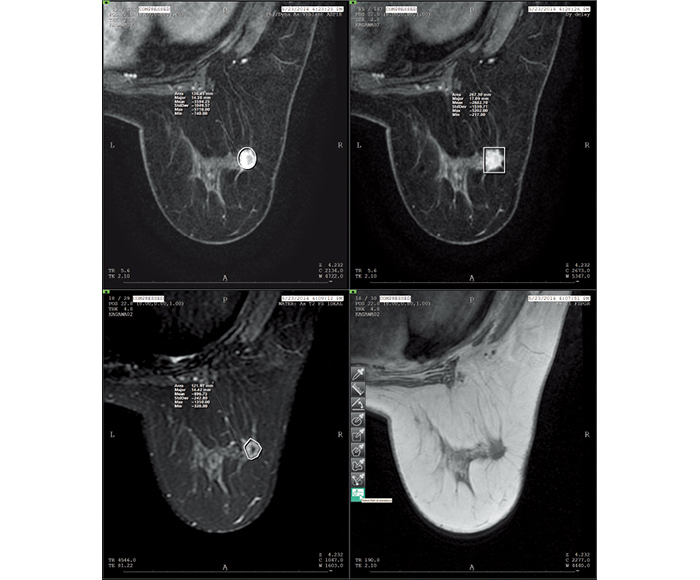

Varias imágenes, como MG, BT, RM, CT, US, etc., están disponibles para el diagnóstico mamográfico al mismo tiempo.

Los valores para la medición de ROI y rayos X pueden obtenerse a partir de la información de cada modalidad de imagen.